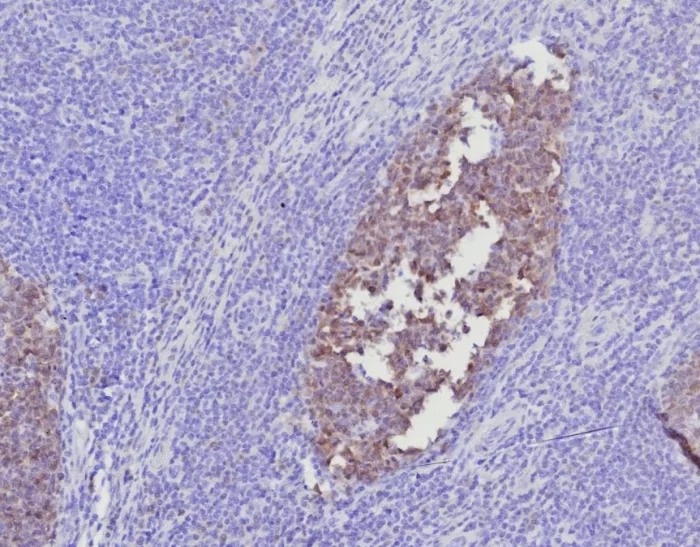

Formalin-fixed, paraffin-embedded human tonsil stained with BOB1 Mouse Monoclonal Antibody (BOB1/7468). HIER: Tris/EDTA, pH9.0, 45min. 2°C: HRP-polymer, 30min. DAB, 5min.

Formalin-fixed, paraffin-embedded human tonsil stained with BOB1 Mouse Monoclonal Antibody (BOB1/7468). HIER: Tris/EDTA, pH9.0, 45min. 2°C: HRP-polymer, 30min. DAB, 5min.

BOB.1 expression in a variety of established B-cell lines, representing different stages of B-cell development, has suggested a constitutive, B-cell-specific expression pattern. LP cells in nodular lymphocyte predominant Hodgkin lymphoma, because they are germinal center-derived, are consistently immuno-positive for BOB.1. Conversely, only some cases of classical Hodgkin lymphoma show BOB.1 immuno-reactivity within the Hodgkin and Reed-Sternberg cells. �Expression of BOB.1 has been reported in follicular center cell lymphoma, diffuse large B-cell lymphoma and some cases of acute myeloid leukemia. �B-CLL, marginal zone lymphoma, and mantle cell lymphoma may show weak to moderate immunoreactivity.